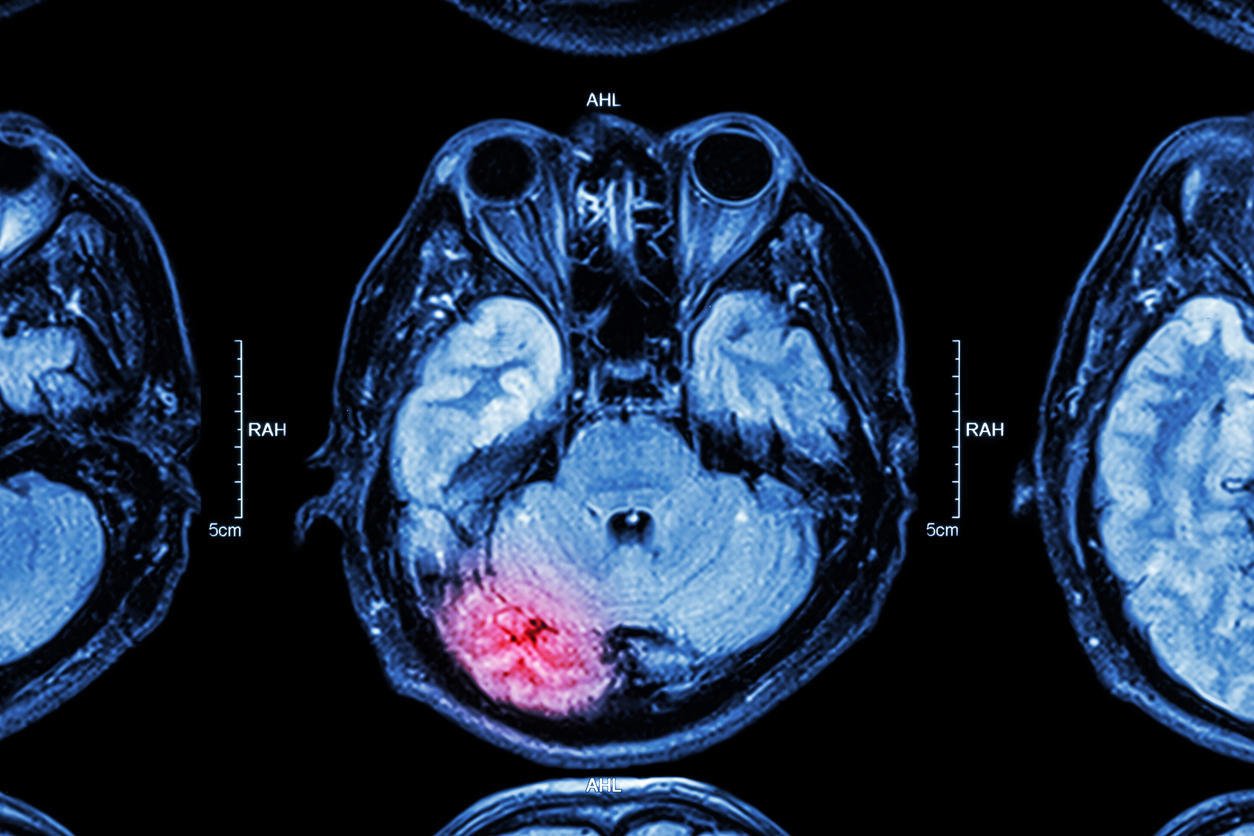

irm de lésion cérébrale cérébrale

Istock

La réussite du traitement dépend de la rapidité de la prise en charge du patient qui fait un accident vasculaire cérébral hémorragique. En effet, plus le patient est traité tôt, moins il aura de séquelles et ses chances de survie seront augmentées. Le traitement, dans un premier temps, a pour but de localiser l'origine de l'hémorragie par imagerie médicale, scanner ou IRM (Imagerie par résonance magnétique). L'arrêt de l'hémorragie, le rétablissement de la circulation sanguine et de la pression artérielle dans le cerveau seront réalisés ensuite par l'administration d'un traitement médicamenteux ou par la chirurgie.